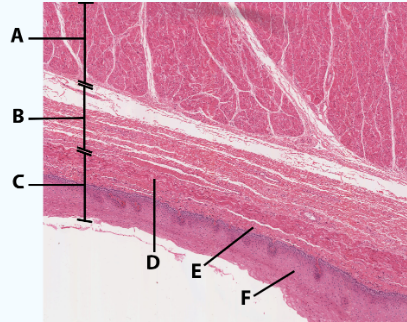

A

Muscularis

B

Submucosa

C

Mucosa

D

Muscularis mucosa

E

lamina propria

F

stratified squamous epithelial tissue

area

Esophagus